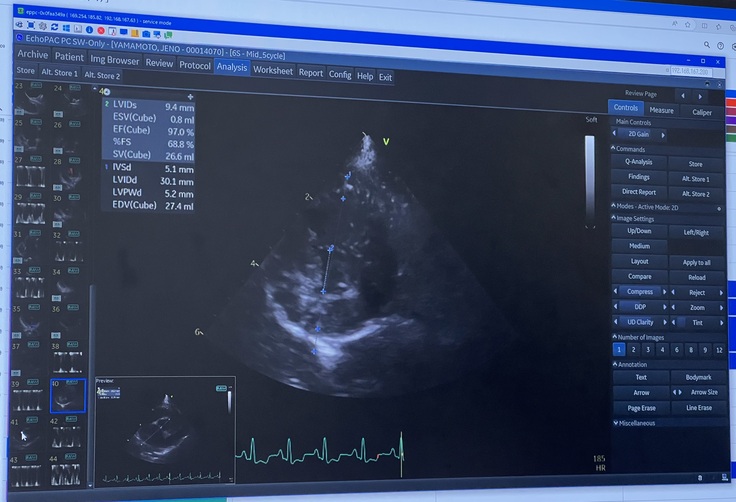

検査の結果は、

初めての「良くなっている」というお言葉をいただきました😭

前回、薬を増やしたおかげで、肥大していた心臓が少し小さくなってくれていました。

そのおかげで弁と言われる血液が一方通行に流れる為のフタのような役割のものが近づいて、逆流を少し防いでくれてるとの事でした。

(※心臓の検査 エコー写真)